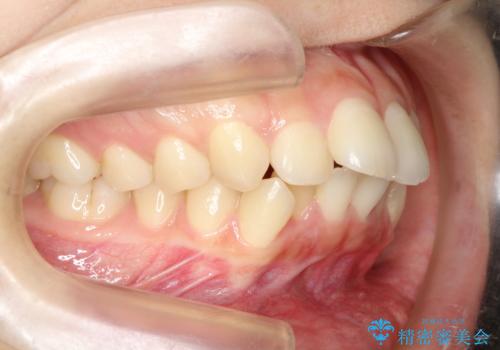

- 口元の突出感を気にして来院された患者様です。

上下左右の第一小臼歯4本を抜歯して口元を下げる治療計画としました。

目立たない装置が希望であったため、上顎が裏側装置である、ハーフリンガル装置を選択されました。